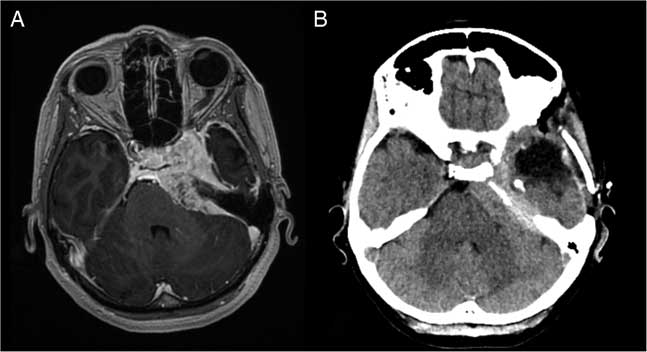

Figure 1 Comparison of axial images before and after left temporal lobectomy. (A) Pre-operative 1.5T T1-weighted post-gadolinium MRI; avidly enhancing left petrous apex meningioma extends along the clivus with mass effect on the left anterolateral aspect of the pons, as well as the inferomedial margin of the left temporal lobe. (B) Post-operative non-contrast CT; hypodense fluid collection in the middle cranial fossa following temporal lobectomy and partially calcified, hyperdense meningioma with mass effect on the adjacent pons.

On brain MRI (Figure 1), the size of the meningioma showed no interval change compared with 3 years earlier. It measured 6.7×3.7×3.0 cm and exerted mass effect medially as described above (with encasement of the left cavernous internal carotid artery) and laterally toward the mesial temporal region. Neuropsychological assessment revealed mild impairments in attention capacity, aspects of executive functions including response inhibition and problem-solving and moderate impairment in visual planning/organization. Verbal memory was average; although left anterior temporal lobectomy would carry a risk of significant verbal memory decline, risk of global amnesia was low. Four seizures were captured on 48-hour ambulatory electroencephalography, all with left temporal lobe origin, in keeping with the likely effect of compression from the meningioma. In discussion with the patient, the decision was made to proceed with a combination of anterior temporal lobectomy and mesial temporal resection. It was made clear to the patient that this was aimed at seizure control rather than improving PBA, although the latter was the more disabling symptom.

At 2 weeks post-operatively, the PBA had essentially subsided, along with the rapid speech and tangentiality. On postoperative CT (Figure 1), the meningioma appeared to exert less mass effect on the brainstem. At 2 months post-operatively, the patient remained seizure free. She noted mild deterioration in verbal memory but was pleased with the outcome in terms of seizure control, affective improvement and quality of life.